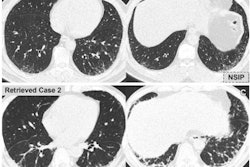

As MinIP has been shown to have a higher accuracy for assessing GGO in comparison with standard MPRs in interstitial lung disease, Booz and colleagues sought to investigate whether it could improve CT's performance in patients with suspected COVID-19.